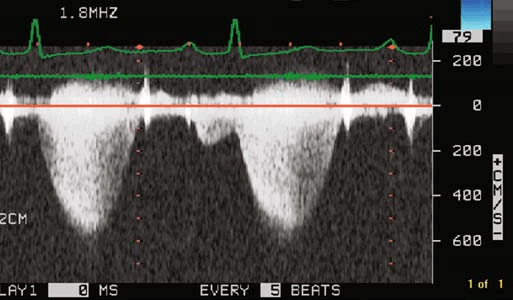

Стеноз легочной артерии является наиболее часто встречающимся пороком развития сердца, который хорошо можно определить на эхокардиографии. Согласно статистике, этот порок вместе с атрезией легочной артерии составляет почти половину всех случаев врожденных пороков сердца. При этом сушение легочной артерии встречается по крайней мере в пять раз чаще, чем полная атрезия. Расположение, размеры и степень стеноза на эхокардиографии бывают разными. По данным эхокардиографии описываются следующие главные типы:

- Сужение инфундибулярной части правого желудочка мышечной пластинкой или фиброзным тяжем (так называемый инфундибулярный стеноз). В некоторых случаях гипертрофическая мышечная или соединительная ткань, создающая впечатление рубца, суживает большую часть инфундибулярного отдела сердца, так что он меняется на эхокардиографии в узкий канал разной длины. Только в редких случаях отмечается стеноз на всем протяжении инфундибулярного отдела. В большинстве случаев инфундибулярный отдел сохраняет коническую форму. С самого начала он постепенно сужается, так что его просвет уменьшается непосредственно под устьем легочной артерии, образуя небольшое отверстие (подклапанный инфундибулярный стеноз). Иногда через гипертрофированную мышечную ткань инфундибулярного отдела проходит несколько узких извитых канальцев неправильной формы, которые открываются в правый желудочек и соединяются друг с другом по направлению к устью легочной артерии. Гораздо чаще сужение распространяется на небольшую часть инфундибулярного отдела, либо в самом его начале (прединфундибулярный стеноз, или стеноз инфундибулярного устья), либо на любое место инфундибулярного отдела, начиная от его устья, вплоть до его конца, непосредственно под клапанами (инфундибулярный стеноз в прямом смысле слова, который может быть высоким, промежуточным или низким). В таком случае инфундибулярный отдел над местом сужения на эхокардиографии бывает расширенным и образует как бы добавочный третий желудочек, величина которого зависит от места сужения. Он достигает наибольших размеров при прединфундибулярном и при низком инфундибулярном стенозе. Таким образом возникает значительное выпячивание части инфундибулярного отдела в вентральном направлении, хорошо заметное эхокардиографическом исследовании. Стенка расширенной части инфундибулярного отдела между местом сужения и устьем легочной артерии может быть утолщенной, состоящей из мышечной ткани, либо утонченной, состоящей из фиброзной ткани.

- Сужение устья легочной артерии на уровне клапанов (клапанный стеноз), возникает в результате слияния створок клапанов, которые в различной мере срастаются своими свободными краями. При максимальном сращении образуется перепончатая перегородка в виде диафрагмы с небольшим закругленным или овальным отверстием, или с поперечной щелью, расположенными в центре диафрагмы или ближе к ее краю. Эта перегородка иногда бывает тонкостенной, нежной и податливой, в других же случаях утолщенной, фиброзной или даже обызвествленной, что можно определить на эхокардиографии. В большинстве случаев перепончатая перегородка со временем вдавливается под влиянием тока крови в легочную артерию в виде воронки или соска грудной железы с небольшим устьем на вершине, расположенным в центре или эксцентрично, причем устье выступает в легочную артерию в виде рыбьего рта. Некоторые авторы считают, что стеноз этого типа возникает в результате внутриутробного воспаления. Доказательство такого образования стеноза является затруднительным. Воспалительное происхождение возможно скорее всего предполагать при чистом стенозе и пульмональной клапанной атрезии или при клапанном стенозе и атрезии легочной артерии, сочетающейся со стенозом и атрезией правого венозного устья.

- Стеноз самого устья, то есть стеноз клапанного кольца, встречающийся на эхокардиографии в редких случаях в качестве изолированного порока, как правило, сопровождает тяжелые изменения инфундибулярного отдела. Может наблюдаться гипоплазия всего клапанного аппарата. Створки клапанов могут быть свободными или спаянными с образованием диафрагмы. Сравнительно часто встречается образование только двух полулунных клапанов, которые могут быть утолщенными и таким образом способствовать сужению правого артериального устья. Часто у одного и того же больного наблюдается стеноз инфундибулярного отдела, устья и клапанов легочной артерии.

На эхокардиографии ствол легочной артерии по сравнению с аортой бывает в подавляющем большинстве случаев уже, иногда по всей длине, или только в некоторых местах, в то время как остальные части могут быть расширенными. Только в редких случаях он бывает нормальных размеров. Ширина ветвей чаще всего пропорциональна ширине ствола, однако в некоторых случаях даже при значительной гипоплазии ствола обе ветви могут быть развиты нормально. Ширина обеих ветвей легочной артерии может быть весьма разной.